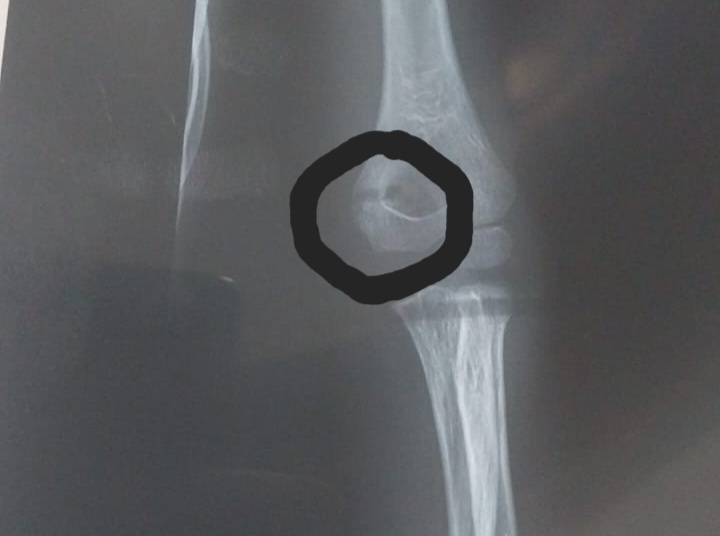

Вот эта широкая "трещина" оказалась совсем не трещиной

Я думала, что перелом - это трещина, которую я обвела в кружочек. Но решила, что она плохо видна, потому что трещина с другой стороны.

А доктор объяснил, что это никакая не трещина, а тень. А формально переломом то, что произошло, можно назвать, но от кости откололся малюсенький кусочек буквально в 1мм. То есть ребенок локтем упал на что-то острое (как край бордюра) и появился вот такой вот скол:

Вот в этом кружочке видите, кость не совсем ровно идет? Это и есть тот самый "перелом"

А сама кость цела, там даже трещины нет. И что в принципе в таких случаях достаточно с повязкой дней 5 походить, чтобы руку сильно не беспокоить.